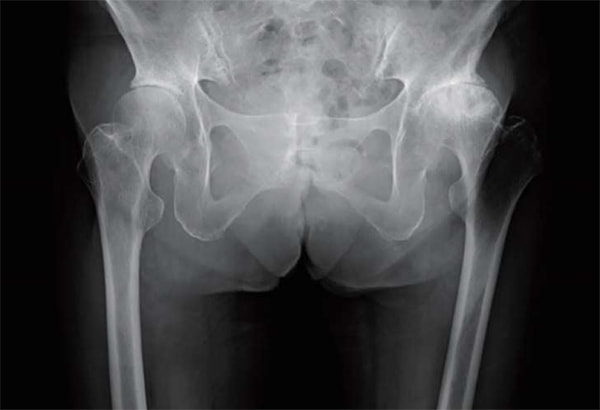

人工股関節置換術において従来の後側方アプローチ(Posteo Lateral Approach)に加えて、2015年より前方アプローチ(Direct Anterior Approach)を積極的に取り入れて参りました。

これは脱臼率の低下に加えて、筋間アプローチによる低侵襲手術を提供するという目的によるものです。これにより在院日数は低下し、術後の姿位制限を撤廃したことで、前述のスポーツ復帰率の向上を図ることができるようになりました。また、高齢化に伴い生じる脊椎変形、脊椎固定術後の矢状断アライメントの変化に対応できるよう、CUPは透視を用いて動的に評価しながら至適位置に設置することで良好なstabilityが得られています。

仰臥位股関節Xp

立位股関節Xp

立位で骨盤後傾を伴う

術後 立位股関節Xp